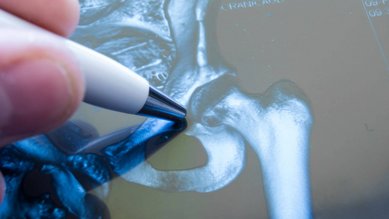

الكسور بالقرب من مفصل الورك

عندما يسقط كبار السن، غالبًا ما يتعرضون لكسر في العظام بالقرب من منطقة الورك، مثل كسر عظام الفخذ. وعادةً ما يتطلب مثل هذا الكسر الخضوع لعملية جراحية.

الفصال العظمي في الورك (داء مفصل الورك)

غالبًا ما يبدأ الفصال العظمي في الورك بشكل خادع. والألم عند الحركة من العلامات الأولية. أهم الإجراءات تشمل العلاج بالتمرينات وتناول مسكنات الألم التي تسمى مضادات الالتهاب غير الستيرويدية (NSAR).